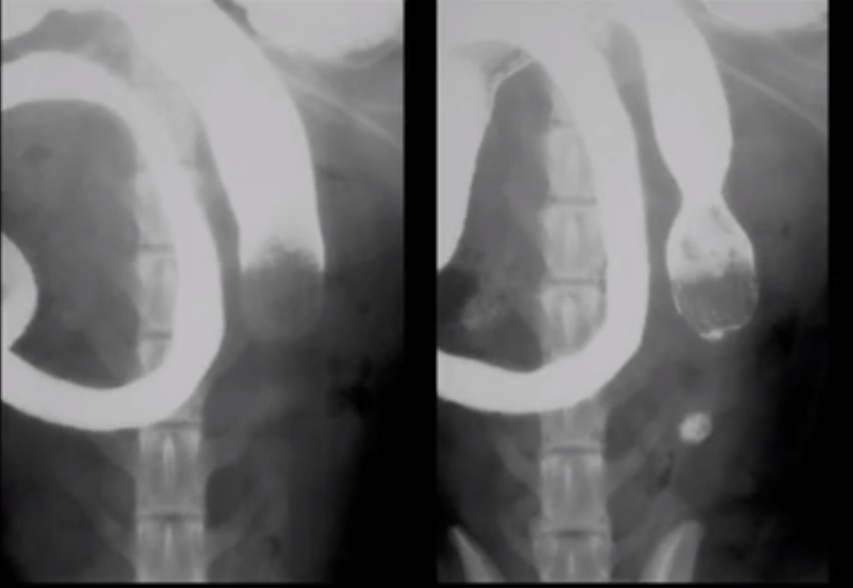

What does this image show?

Displacement of stomach by hepatic mass?

Normal dog stomach mucosa using double contrast gastrogram